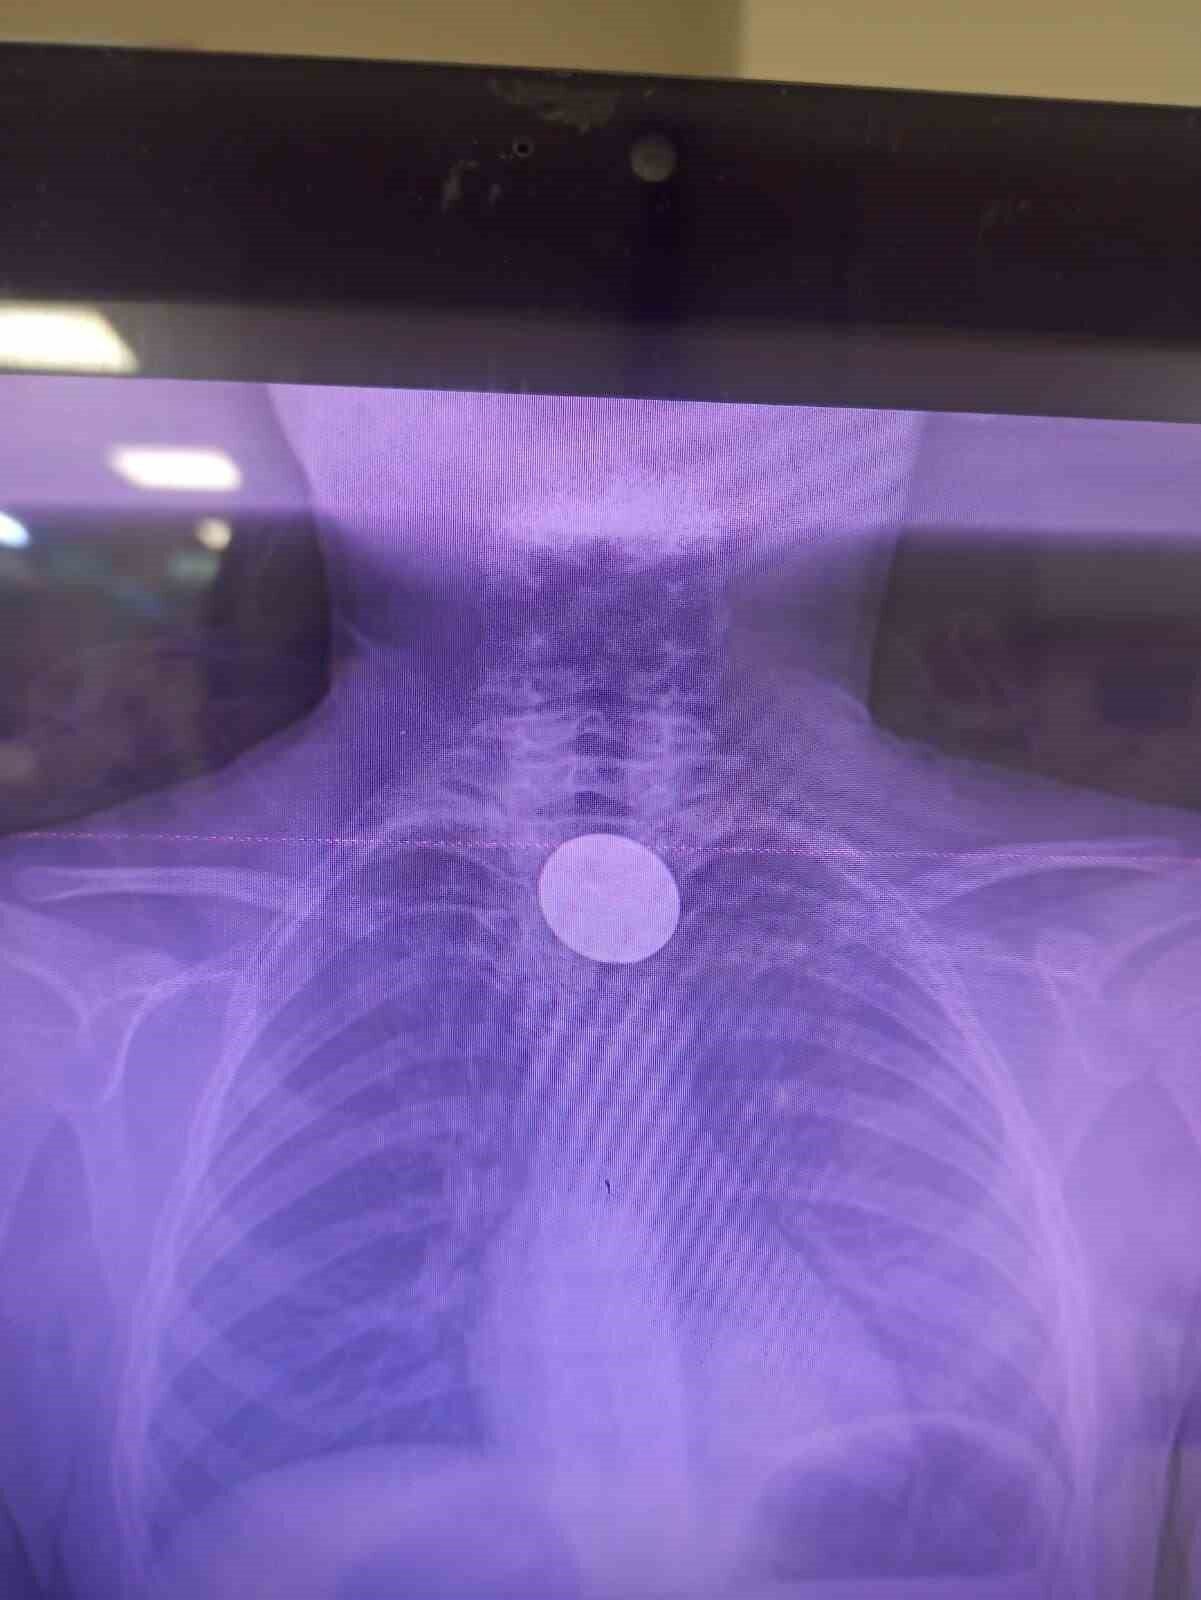

Siirt’te boğazına madeni 5 lira kaçan 8 yaşındaki çocuk, hastanede doktor müdahalesiyle kurtarıldı.

Yabancı cisim yutma şikayetiyle ailesi tarafından Siirt Eğitim ve Araştırma Hastanesi’ne getirilen 8 yaşındaki Y.K., yapılan ilk değerlendirme ve görüntüleme tetkiklerinin ardından ilgili branşlarca operasyona alındı. Y.K.’nın yemek borusuna kadar ilerlediği belirlenen madeni para, gastroenteroloji uzmanı Dr. Yaren Dirik ve kulak burun boğaz hekimi Yasin Gökçınar tarafından müdahale edilerek çıkartıldı. Operasyonun ardından bir süre gözlem altında tutulan Y.K., tedavisinin tamamlanmasıyla taburcu edildi.

Siirt Eğitim ve Araştırma Hastanesi Başhekim Yardımcısı Uzman Dr. Burak Özkan, çocuk hastalarda yabancı cisim yutma vakalarının ciddi riskler oluşturabileceğini ifade etti. Uzm. Dr. Özkan, “Hastanemize başvuran 8 yaşındaki hastamızın yemek borusuna kaçan madeni para, gastroenteroloji ve KBB ekiplerimizin koordineli ve titiz çalışmasıyla herhangi bir komplikasyona yol açmadan başarılı bir şekilde çıkarılmıştır. Operasyon süreci sorunsuz geçmiş olup hastamızın genel durumu iyidir” şeklinde konuştu.